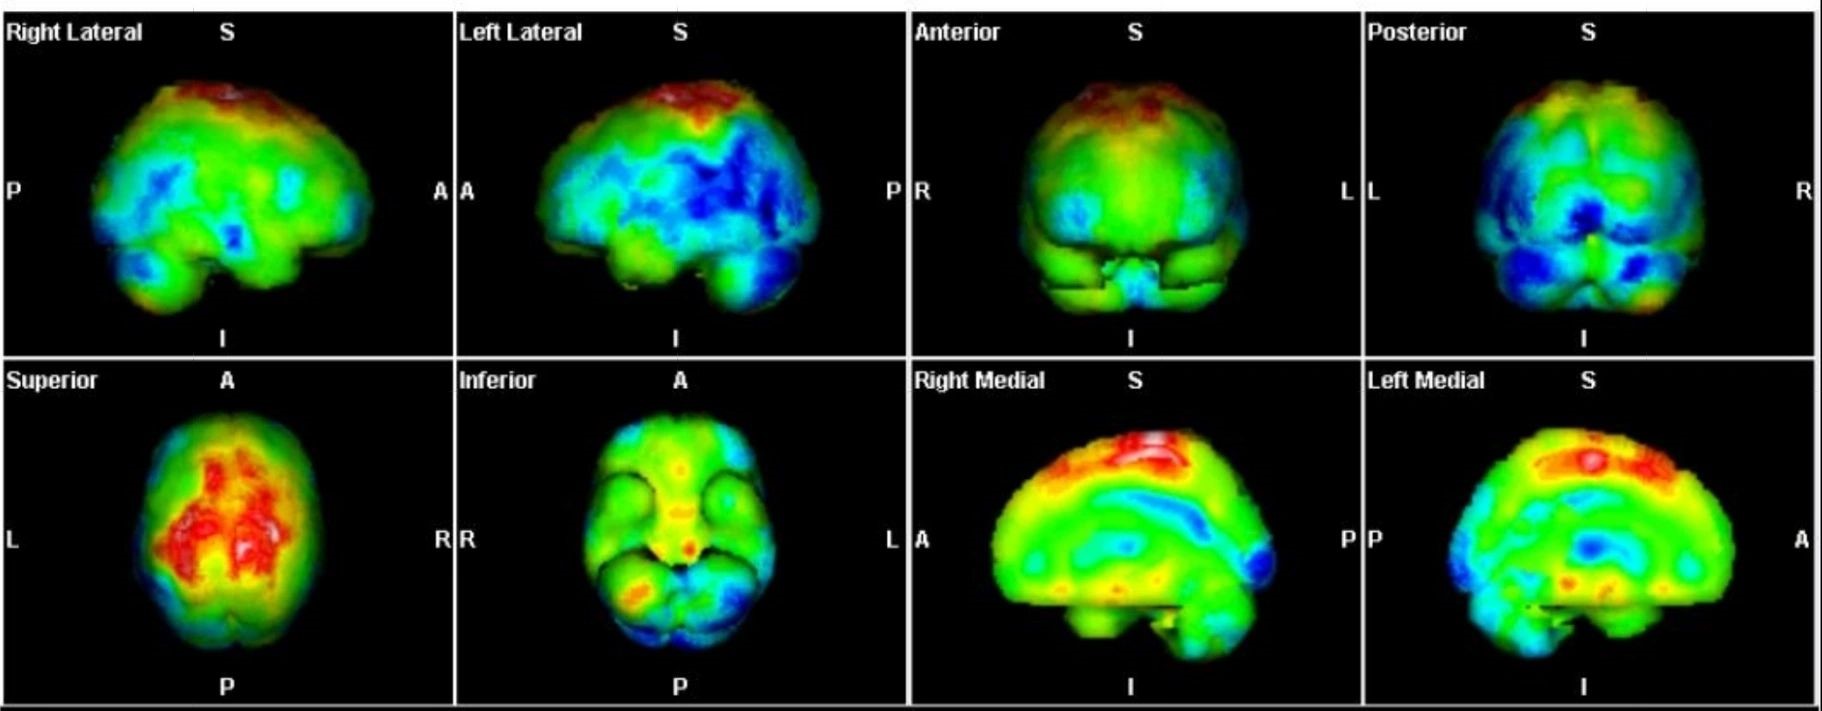

Οι περισσότερες διαγνωστικές εξετάσεις της Πυρηνικής Ιατρικής είναι γνωστές ως σπινθηρογραφήματα, τα οποία στη σύγχρονη εποχή πραγματοποιούνται με τη βοήθεια της γ-κάμερας (γ-camera) ή συστημάτων SPECT/CT, που επιτρέπουν απεικόνιση υψηλής ακρίβειας και λειτουργική ανάλυση σε μοριακό επίπεδο.

IQ SPECT Η τέχνη της ελαχιστοποίησης της δόσης με ταυτόχρονη μεγιστοποίηση της ταχύτητας Στη σύγχρονη Πυρηνική Ιατρική, όπου η ανάγκη για ταχύτερες και ασφαλέστερες μελέτες Μυοκαρδιακής Αιμάτωσης (MPI) αυξάνεται διαρκώς, το IQ SPECT αποτελεί μία από τις πλέον ώριμες και καινοτόμες τεχνολογίες. Η αρχή του είναι απλή και καθαρή: να συλλέγει όσο το δυνατόν περισσότερα δεδομένα από την καρδιά, με την ελάχιστη δυνατή δόση και στον ελάχιστο χρόνο, χωρίς συμβιβασμούς στην ποιότητα εικόνας. Minimum dose & maximum speed Στις συμβατικές SPECT καρδιάς, μεγάλο τμήμα του ανιχνευτή δεν αξιοποιείται λόγω του μικρού μεγέθους του εξεταζόμενου οργάνου. Αυτό οδηγεί σε παρατεταμένο acquisition – πολλές φορές έως 16 λεπτά – ώστε να εξασφαλιστεί η αναγκαία ποιότητα εικόνας. Το IQ SPECT υπερβαίνει αυτόν τον περιορισμό. Με βελτιστοποιημένο χειρισμό της γεωμετρίας, των collimators και του acquisition, μεγιστοποιεί τα ανιχνευόμενα δεδομένα από την καρδιά, επιτρέποντας ολοκληρωμένη μελέτη σε λιγότερο από 5 λεπτά, μείωση της χορηγούμενης δόσης έως και 75%, και διατήρηση ή και βελτίωση της ποιότητας εικόνας.

Όλες οι μελέτες Πυρηνικής Ιατρικής πραγματοποιούνται με SPECT/CT μέθοδο στις 2 υπερσύγχρονες SIEMENS Pro SPecta. Από το δυσδιάστατο στο τρισδιάστατο, από την υπόνοια στη βεβαιότητα.

Οι μελέτες μυοκαρδίου πραγματοποιούνται με τη χρήση της μοναδικής τεχνολογίας IQ SPECT που εξασφαλίζει μικρό χρόνο απεικόνισης – μικρή δόση – υψηλή διακριτική ικανότητα/ανάλυση.